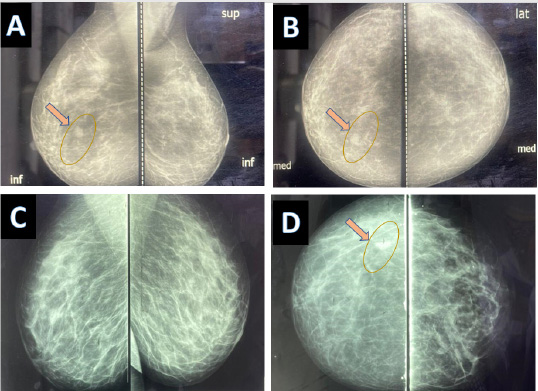

Since the 1960s, mammography has evolved as a key tool in managing diseases, complementing clinical examination and biopsy. Fig. (5) for normal mammography and Fig. (6) for mammography of FBC. Later, ultrasound (introduced in the 1970s–1980s) was performed. Fig. (7) shows a breast ultrasound with a typical FBC. In the 1990s, MRI was introduced, further improving diagnostic accuracy and helping to exclude unnecessary biopsies [15]. Table 2 summarizes the key aspects of each imaging modality used for FBC. Imaging plays a vital role in patient screening, guiding breast biopsies, and confirming definitive histological diagnoses. Moreover, its significance extends beyond diagnosis, as it is essential for patient follow-up and ongoing therapeutic planning [16]. By enabling the tracking of fibrocystic breast changes (FBC) over time, clinicians can monitor FBC progression and regression, facilitating informed decision-making and improving patient outcomes.

(A, B) Mammography of 27 years old lady with fibrocystic changes of the breast, a small cyst is observed on the medial aspect of the breast (C, D) Mammography of a 43 years old lady with fibrocystic changes of the breast, a small cyst is observed on the lateral aspect of the breast.